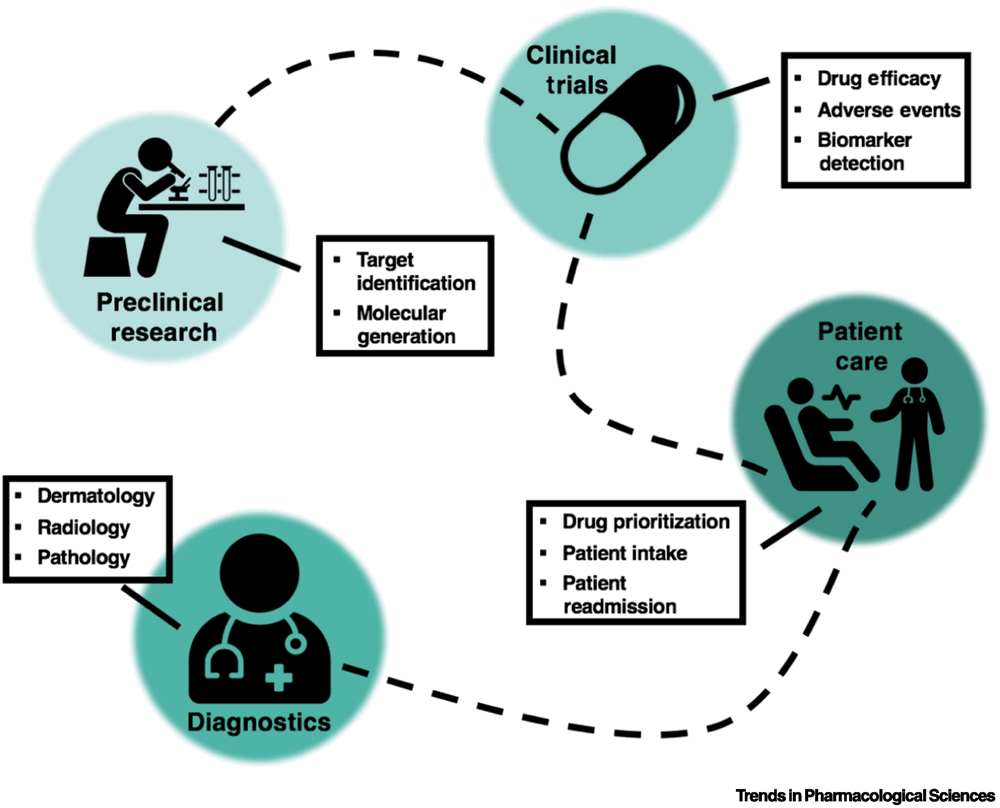

2.何时以及如何使模型可解释

何时承担可解释性的重担

关于AI(尤其是DL)与医学的集成的最大批评之一是认为AI是“黑匣子”。这是指这些算法如何进行预测时缺乏明确性和透明度,这归因于DL要求大量变量(即每个神经元的权重)和复杂的基础结构(体系结构,损失函数,激活函数等)。缺乏模型的可解释性导致科学界显着地退缩,因为很多时候,预测背后的“原因”与预测本身一样重要。这是该领域内一个经过认真辩论的主题,其中许多都指向由于伪像而实现高精度的模型示例。例如,如果一个人试图预测患者的白细胞计数并使用一天中的时间作为输入,那么这可能会导致表面上较高的准确性,因为AI知道后来抽血会导致白细胞计数较低。该结果是由混杂影响所驱动的,在大多数医院中,深夜抽血大多是在紧急情况下进行的,在紧急情况下患者更可能有较低的白细胞计数。尽管此类因素可能有助于提高报告的准确性,但它们在前瞻性预测中实际上没有用。

当前,有大量的研究工作正在打开难以解释的模型的黑匣子。许多人希望为临床任务建立可解释的DL模型可以帮助加速这些方法在现实世界中的实施。如果临床医生可以轻松地理解为什么模型预测了某种诊断/预后,他们将更愿意将其用于实际患者,因为他们可以减轻对模型完全基于伪影进行预测的担心。但是,在诸如AI在诊断中的应用的情况下,建议的工作流程将用于预测模型以指导人类决策,而医师/医学专家会审查每个单独的预测,因此限制了模型完全透明的必要性。例如,当前正在进行的一项临床试验(临床试验编号:NCT03705650)正在测量EchoGPS(一种由AI驱动的软件)在非超声检查专家从超声图像中检测某些心脏疾病时的有效性。该软件仅在评估超声时指导医疗专业人员,而不是替代人类的诊断。当然,当牺牲任何数量的可解释性时,都需要权衡取舍,尽管准确性可能更高,但是可能会保留系统性的偏差,否则可能会被捕获。因此,在选择如何优先考虑模型可解释性时,了解给定模型将如何应用于现实环境中非常重要。

可解释性和透明度特别重要的医学领域之一是临床前和早期药物开发。这里需要可解释的模型,不仅要避免模型依赖无关变量的可能性,而且要揭示潜在的作用机理,更好理解可能会导致更好的药物定位和毒性意识,最终助长下一代候选药物的产生。因此,旨在回答诸如“该药物是否具有毒性”或“该药物对哪种疾病有效”之类的方法的方法应确保可以清楚地阐明模型背后的原因。对模型可解释性的这种尽职调查和优先级排序可以通过更全面地了解化合物、靶标或疾病来增强AI驱动的药物开发。